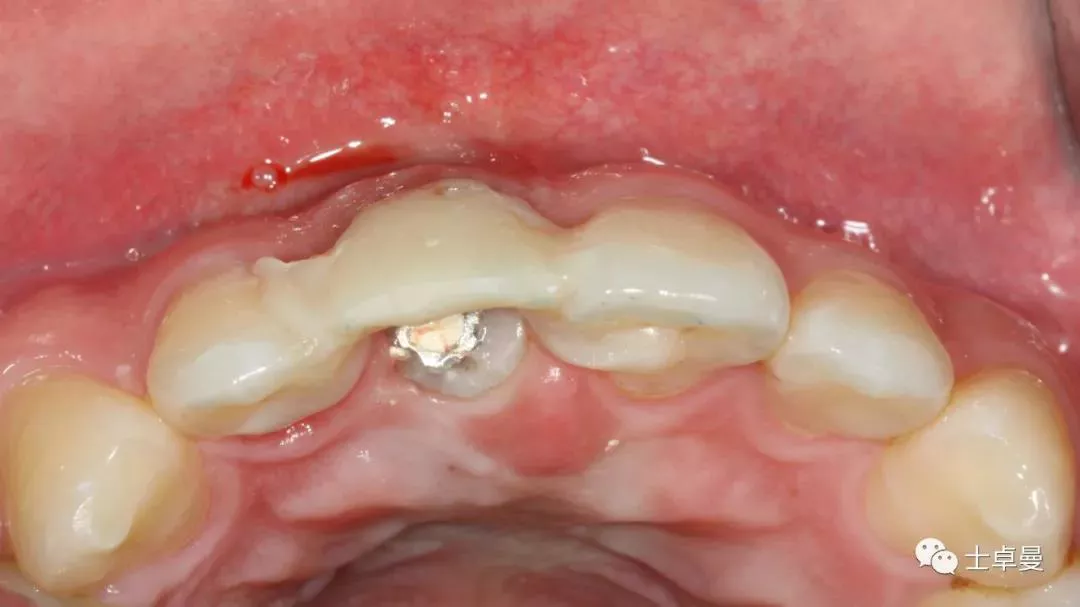

种植体植入后,植体唇侧间隙内填塞骨粉0.25g,胶原骨100mg,安放愈合帽,明胶海绵暂时封闭创面

术后即刻CT示,种植体植入位置理想

术后即刻制作个性化愈合帽

上部制作马里兰桥临时修复体